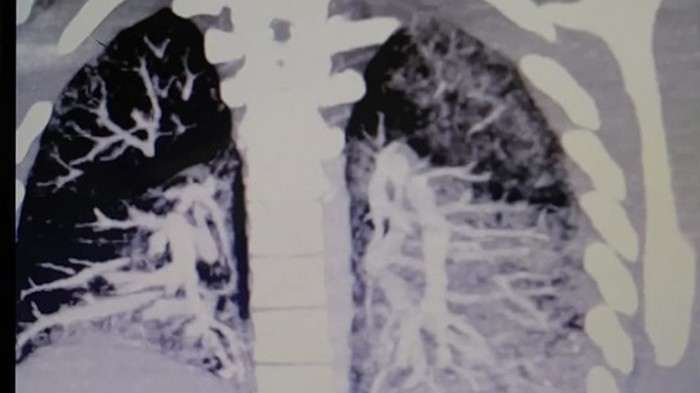

Врачи обнаружили в легких парня застывшее масло для вейпа. Они сравнили его с застывающим бетоном. Врачи ищут способ вновь "растопить" масло и вывести его из легких.

Сообщается, что парень регулярно курил вейп на протяжении двух лет. Сейчас его легкие похожие на легкие 60-летнего человека, выкуривающего по две пачки сигарет в день.

Специалисты подчеркивают, что из легких Майо выходила жидкость кроваво-красного, коричневого и темно-зеленого цвета. При этом его легкие получили такой ущерб, что орган может уже не восстановиться.